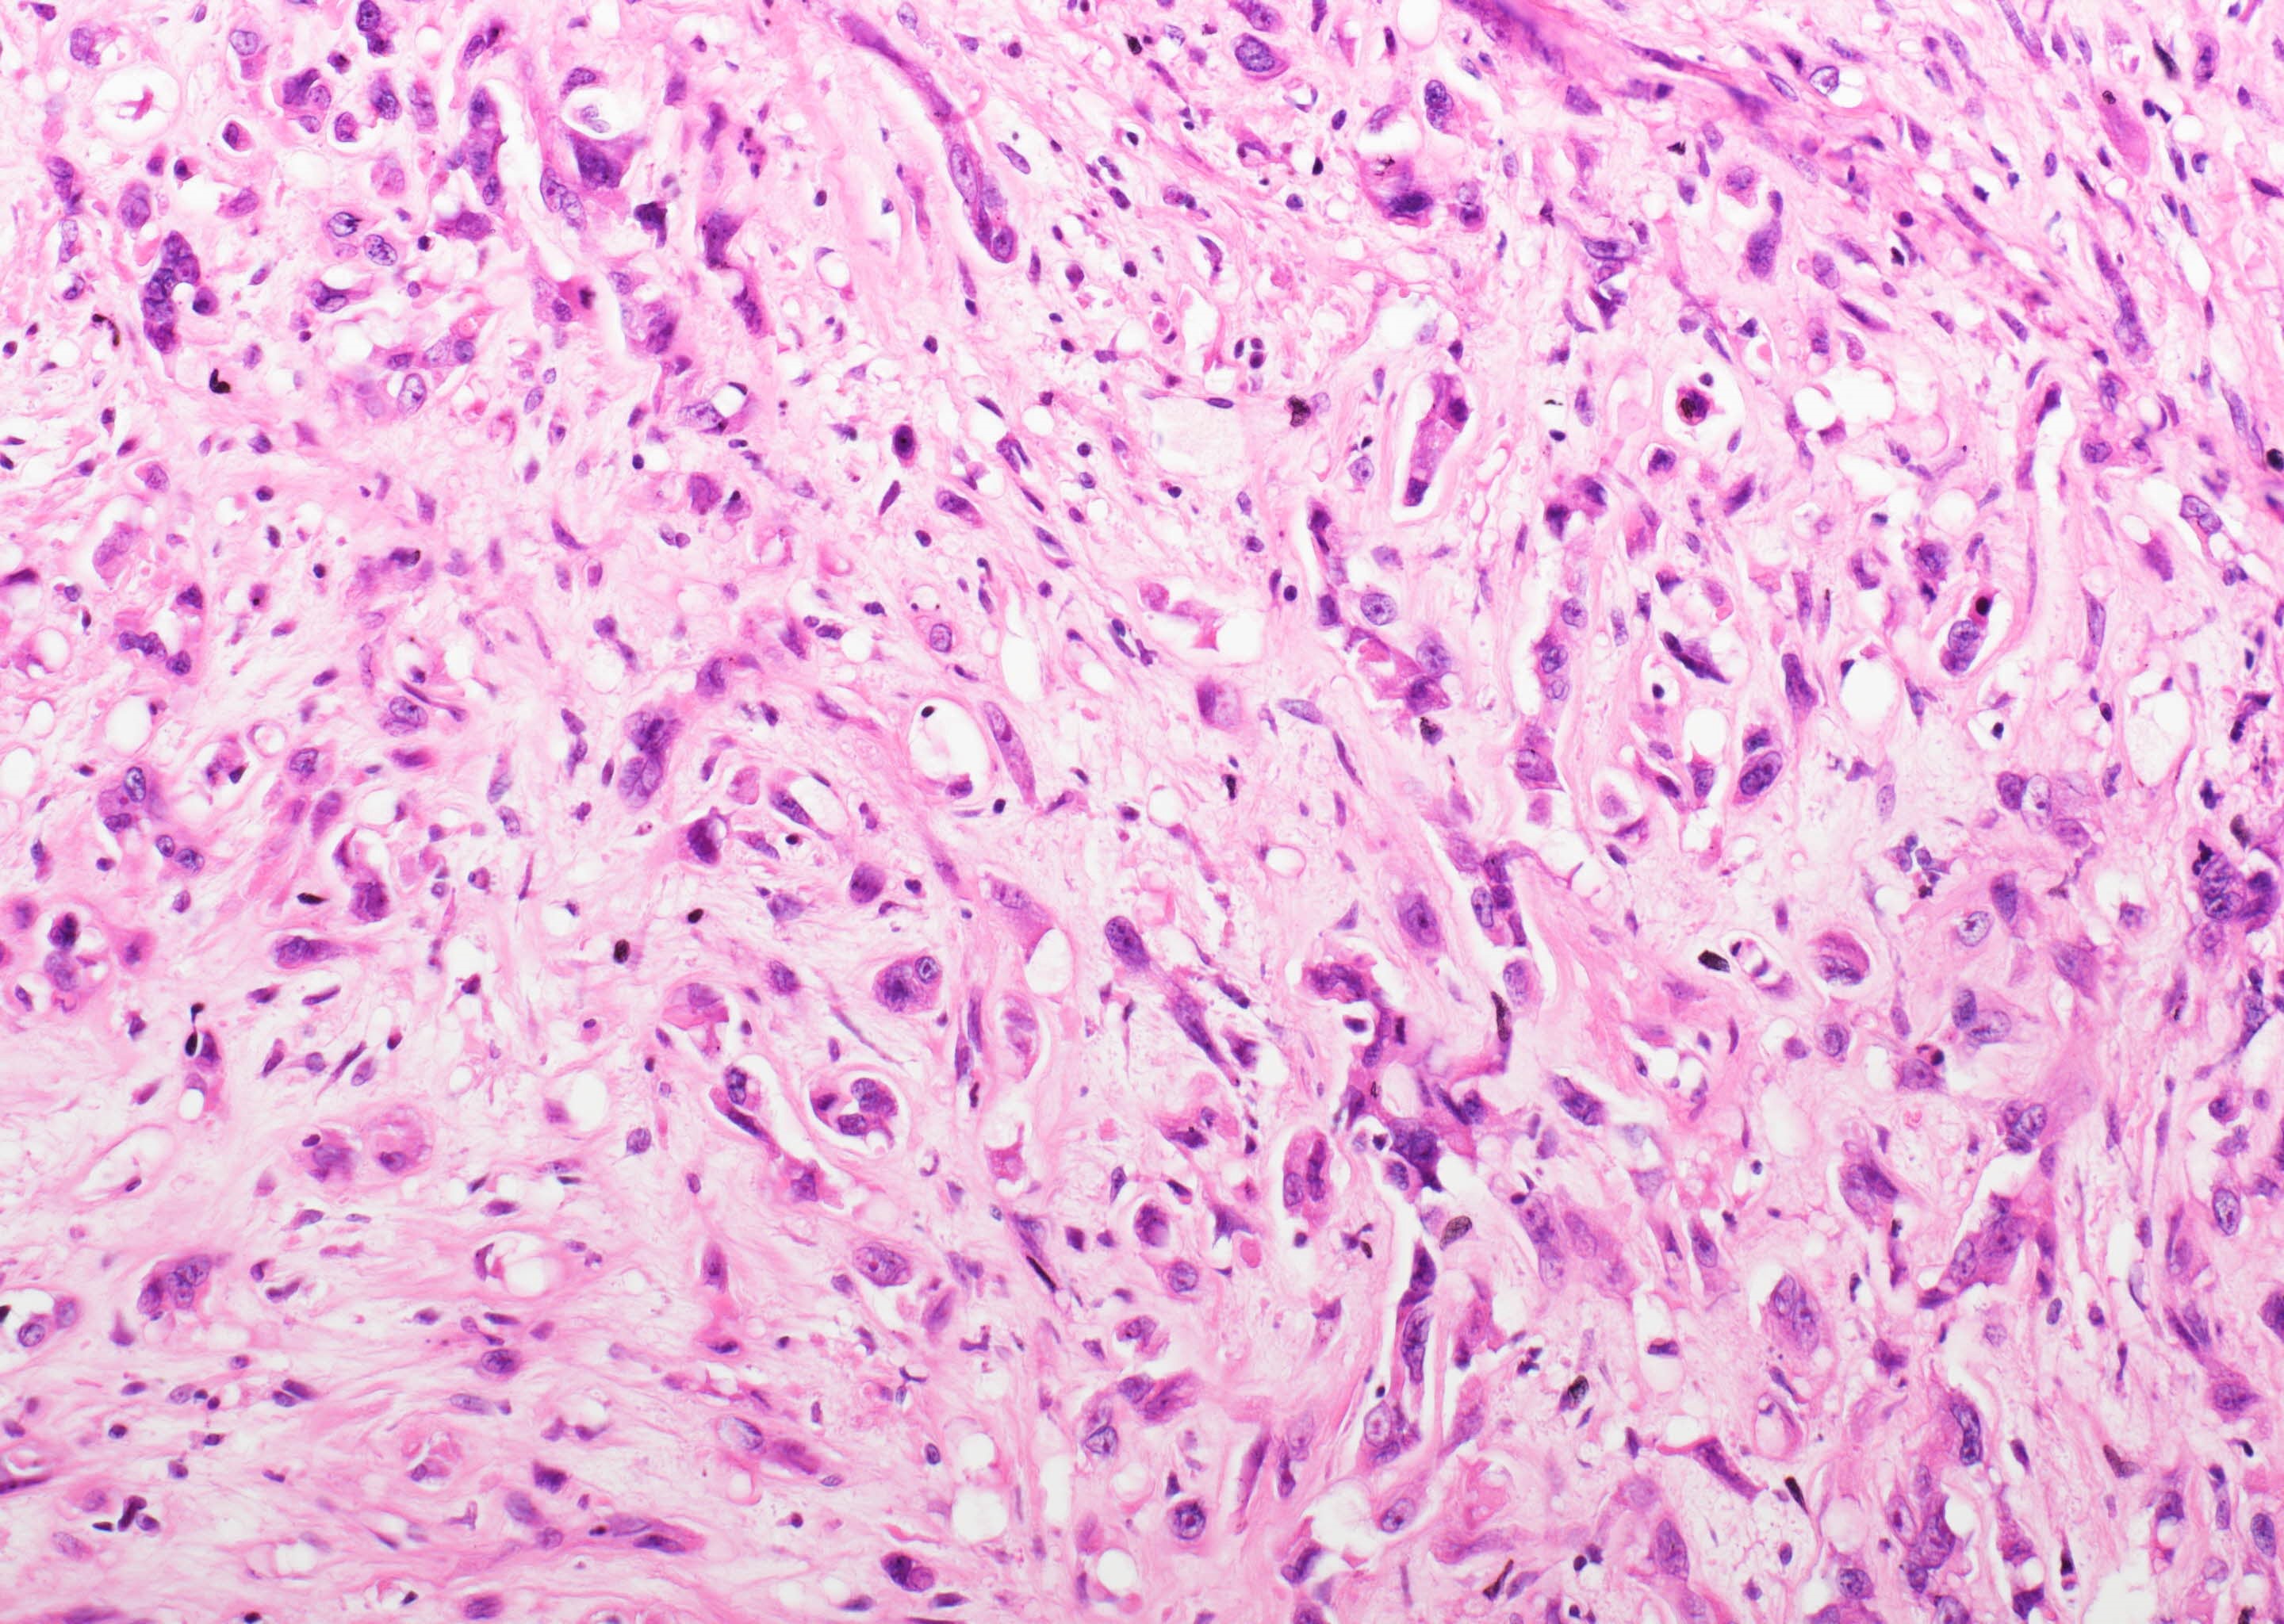

- YAP-TFE3 subtype:

- Solid nests or pseudo alveolar arrangement of epithelioid cells enmeshed in a fibrous stroma

- Tumor cells have abundant, densely eosinophilic cytoplasm and can form vascular spaces

- Intracytoplasmic vacuoles are rare

- Usually minimal mitotic activity, atypia or necrosis

- Up to 10% of cases exhibit frank malignant features of prominent nuclear pleomorphism, increased mitotic activity, solid growth or necrosis; these tumors resemble epithelioid angiosarcoma and have a more aggressive behavior (Am J Surg Pathol 2008;32:924)

Microscopic (histologic) images